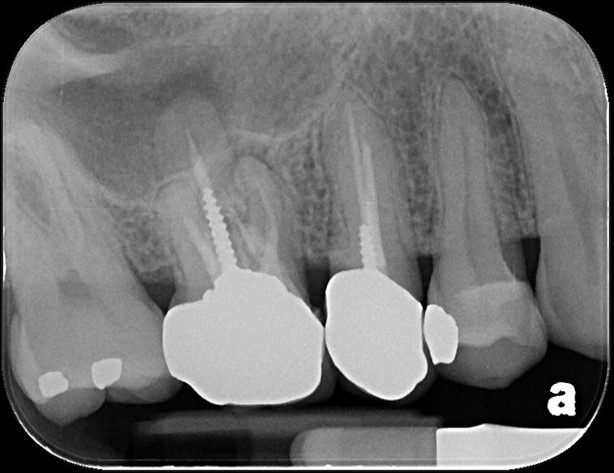

治療前,第一大臼齒根尖病變

顯微根管重治療

鑄造金屬釘柱